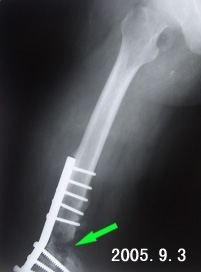

治療:無移位或輕度移位的股骨髁骨折,抽出關節內積血,加壓包紮。用牽引或石膏托固定4~6周后開始活動膝關節。隨著內固定器材不斷改進,使比較複雜的股骨髁骨折,也能得到較為可靠的內固定,因此當前在治療方面的總趨勢,傾向於手術。手術指征除與一般關節內、關節旁骨折所共有外,在此部位還有以下幾種情況。合併韌帶或半月板損傷,合併嚴重的血管神經損傷,以及骨折塊游離,血液供應不良。內固定方法如下:

(2)鋼板螺絲釘 包括專門用於股骨髁骨折的鋼板螺絲釘與人工彎曲後使其與股骨髁部相適應的普通鋼板。特點是適應性強,使用方便簡單。但在鋼板與螺絲釘的連線部位易出現鬆動,甚至斷裂,故難於保證骨折的部位的穩定,常需與石膏外固定並用。為克服這些缺點,有人已設計出新型的鋼板螺絲釘。此外還有“AO”的T型鋼板,此種鋼板遠端寬,並有多個螺孔,使螺絲釘能從前方或後方導入骨孔,固定股骨髁。

無移位骨折可行石膏固定。單髁、雙髁骨折伴有移位者及髁間粉碎骨折多需開放復位及骨栓、螺釘或鋼板固定,附加 石膏固定4~6周 後早期 功能活動,臨床癒合後方可下地負重。